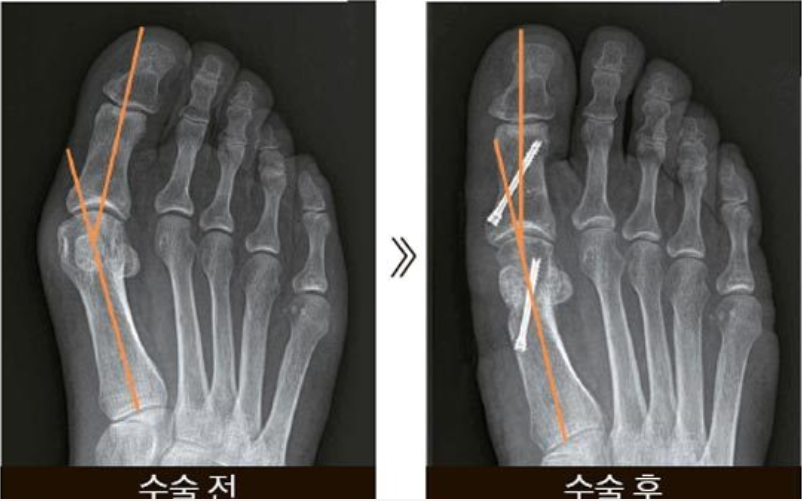

무지외반 수술은 통증이 심해 신발을 신기 불편한 경우, 엄지발가락이 심하게 휘거나 이미 다른 발가락까지 변형된 경우 등으로 고려하게 됩니다. 일반적으로 두출 부위의 뼈를 깎고 내외로 치우친 뼈를 잘라 각을 교정하며 짧아진 근육 및 연부조직을 늘리는 방법으로 보통 2~3일 정도 입원하게 되며 특수화를 착용하고 목발 없이 걸을 수 있습니다.다리 길이보다 발볼을 생각해서 자신에게 맞는 신발을 선택하는 것이 중요합니다. 가능하면 신발은 다리가 부어 있는 상태인 오후 늦게나 저녁에 구입하는 것이 좋아요. 신발깔창을 꺼내서 바닥에 놓고 그 위로 올라갔을 때 발이 깔창에서 잘 나오지 않는 신발을 선택하면 실패할 확률은 거의 없습니다.